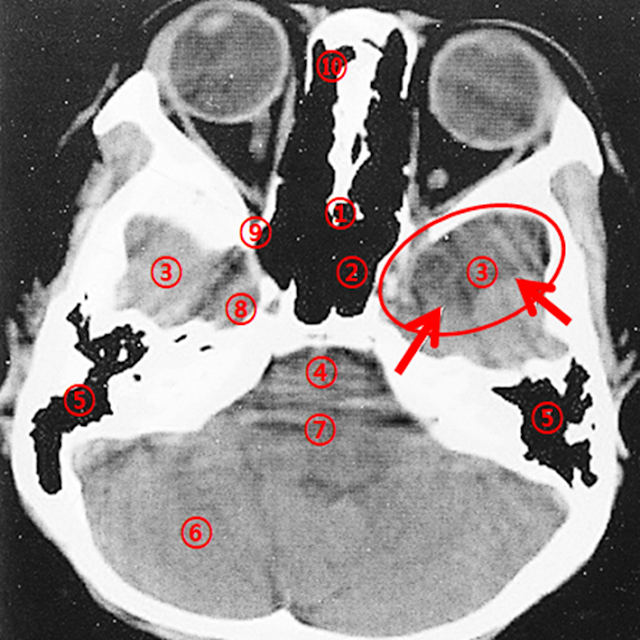

Axial Section Passing Through the Petrous Part of the Temporal Bone

Case: A 10-year-old male with a well-defined Low Density Area (LDA) observed in the left middle cranial fossa.

A well-defined low-density area (LDA) is noted in the left middle cranial fossa (red arrow). The sphenoid bone appears slightly thinned. These findings are suggestive of an arachnoid cyst, which commonly occurs in the middle cranial fossa. Although chronic infarction or contusion may be considered as differential diagnoses, the thinning of the adjacent bone increases the likelihood of an arachnoid cyst. Bone setting views can provide additional diagnostic value.